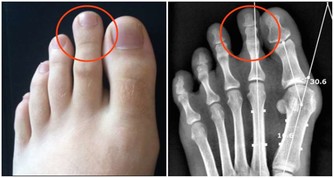

首先是孩子長高的原理,孩子長高其實就是將骨骼拉長,

所以媽媽們就要想辦法讓孩子的骨骼發育長長。

而骨骼的發育就少不了鈣的吸收,所以長高的前提是補鈣。